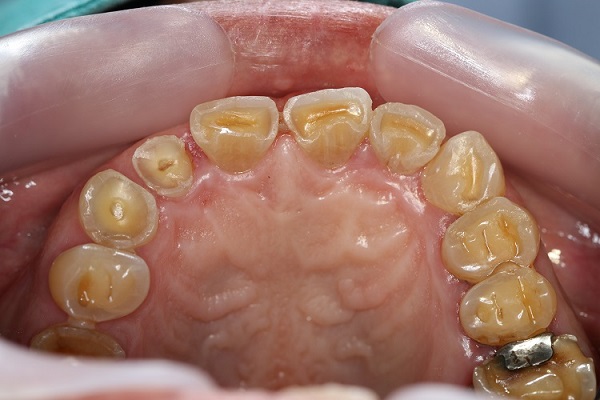

from 32smiledesign.com.au

Dental erosion involves the softening of the tooth surface by acidic substances of intrinsic or extrinsic origin, or a combination of both. The nomenclature and classification of dental erosion commonly used in the dental literature are summarized. The nomenclature and classification of dental erosion commonly used in the dental literature are summarized. They are based on etiology (extrinsic,. The nomenclature and classification of dental erosion commonly used in the dental literature are summarized. The nomenclature and classification of dental erosion commonly used in the dental literature are summarized. They are based on etiology. They are based on etiology. European journal of oral sciences , volume 104. Early clinical signs of dental erosion are characterized by loss of enamel texture, a silky glossy appearance, and sometimes a dulling of the surface gloss, referred to as the “whipped clay.

Dental Erosion and Dental Abrasion 32 Smile Design Schofields Dentistry